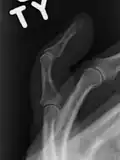

The diagnosis is generally based on symptoms and supported by X-rays.[3] The injury can be accompanied by swelling and ecchymosis.[4]

X-ray showing fracture at the insertion of the extensor tendon